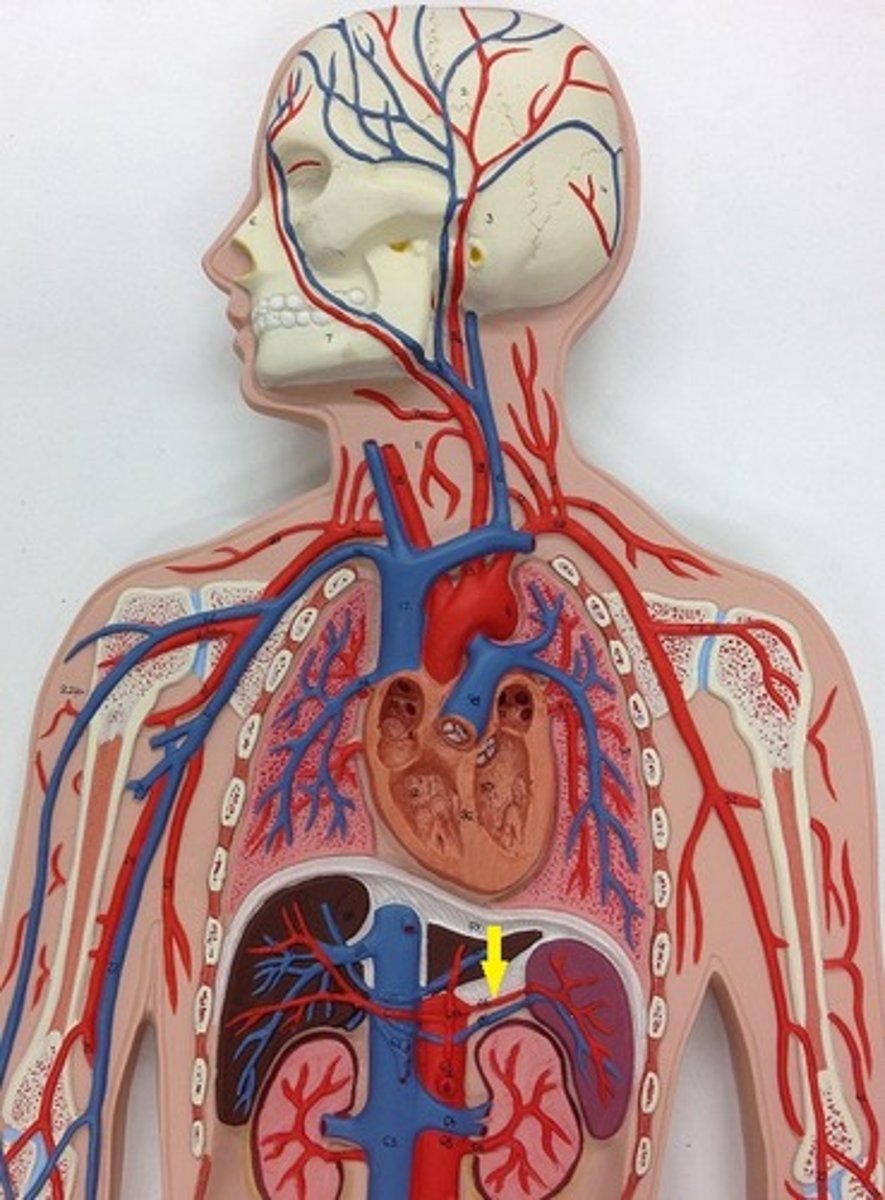

splenic artery

-extends from the celiac trunk to the splenic hilum.

-supplies to the spleen

splenic hilum

site located in the middle of the spleen where blood vessels, lymphatic vessels, and nerves enter or exit the organ.

splenic vein

-Fuses with the superior mesenteric to carry newly filtered blood to the hepatic portal which will bring it to the liver

How would the average age of red blood cells in the splenic artery compare to the average age of red blood cells in the splenic vein?

The average RBC age will decrease because the spleen would have removed many of the oldest RBC's.